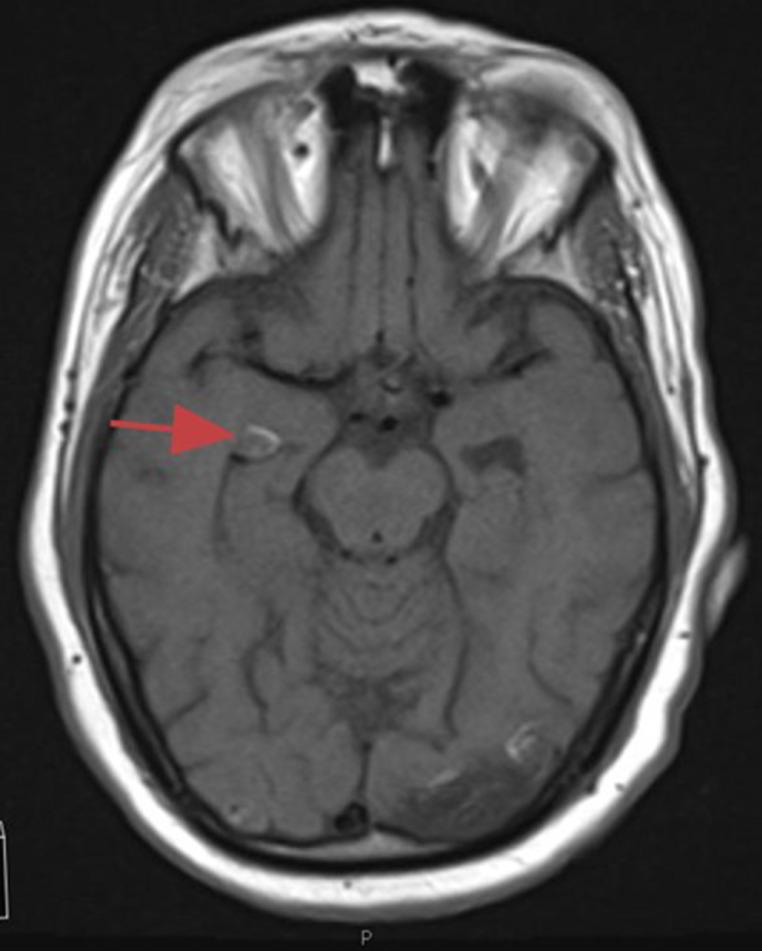

Here we describe two, separate, and unique radiological findings in two distinct patients, sequelae from prior silicone oil injection for management of retinal detachment. In both cases we present bilateral, frontal horn hyperdense "masses" without appreciable enhancement or surrounding vasogenic edema. Both cases serve as important reminders of the potential for silicone oil migration and its unique radiological presentation, which has the potential to be a radiologic mimic of intracerebral hemorrhage and significantly change medical management of individuals presenting with transient ischemic attack or cerebrovascular accident.

在此,我们描述了两名不同患者身上出现的两种独立且独特的放射学表现,这是先前为治疗视网膜脱离而注射硅油的后遗症。在这两个病例中,我们均发现双侧额叶角有高密度“肿块”,无明显强化或周围血管源性水肿。这两个病例都有力地提醒我们,硅油有迁移的可能性及其独特的放射学表现,这有可能在放射学上被误诊为脑出血,并显著改变患有短暂性脑缺血发作或脑血管意外患者的医疗管理。